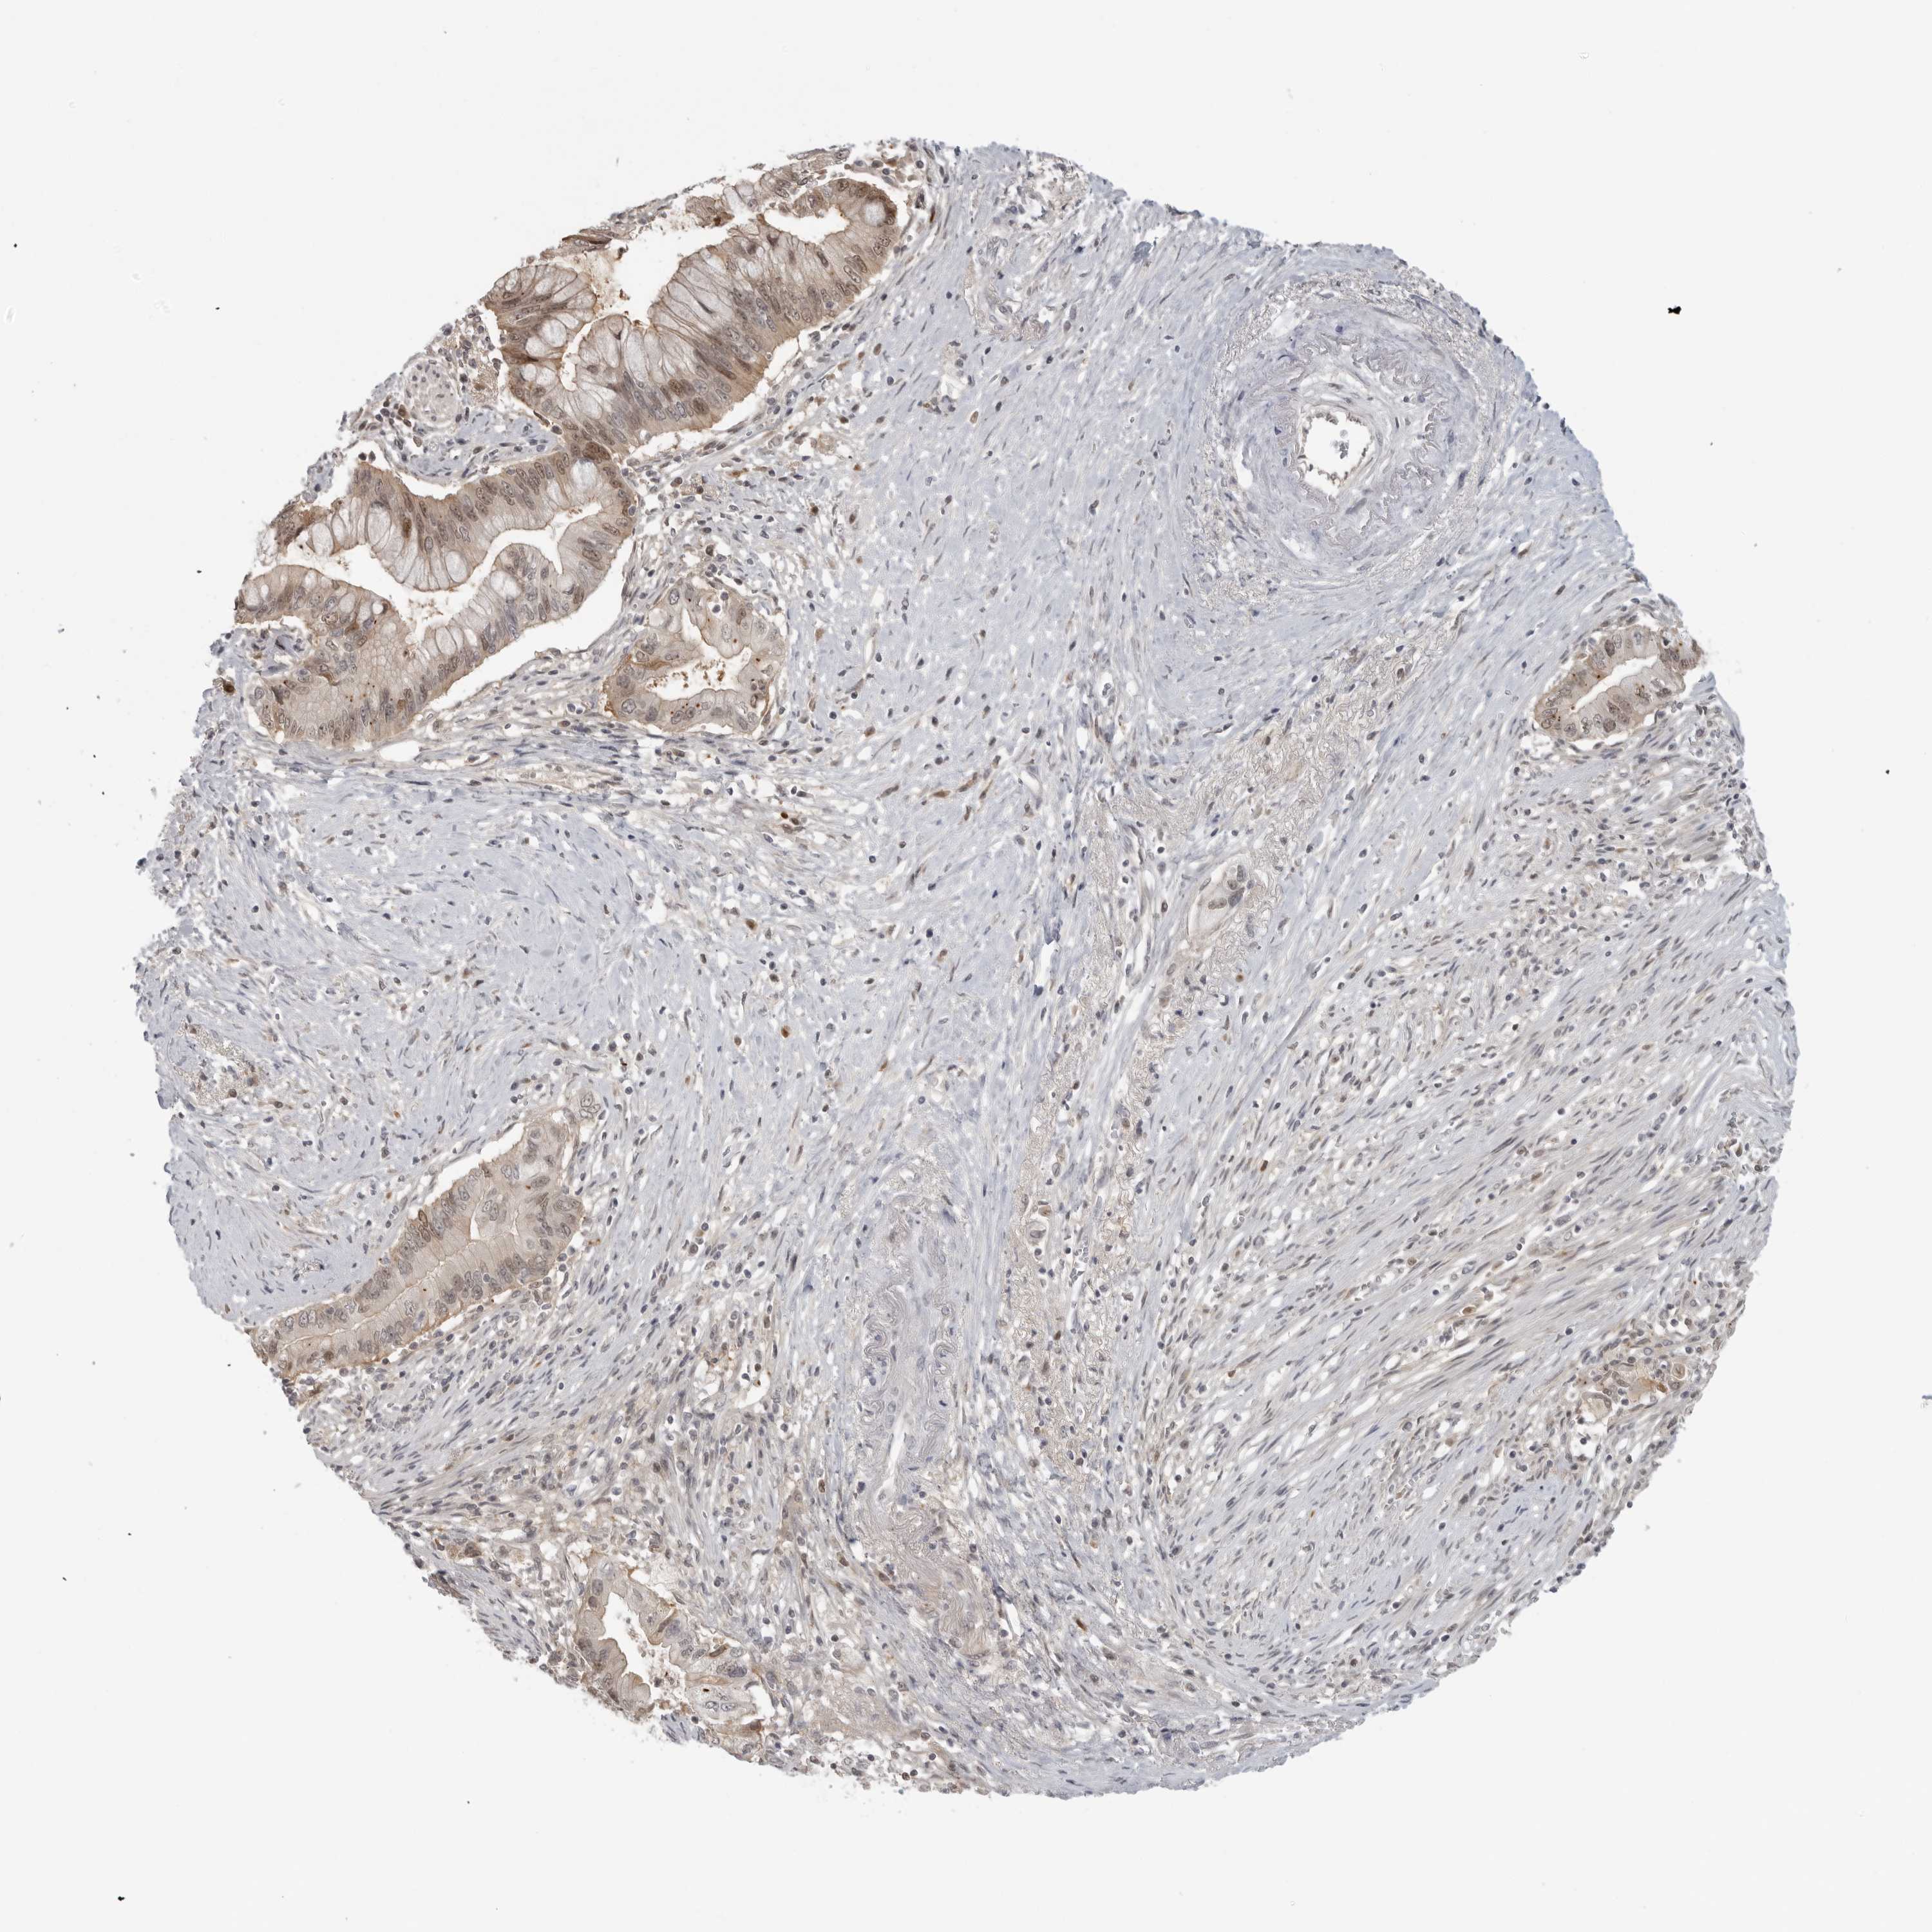

PANCREATIC CANCER - Protein expressioni

A mouse-over function shows sample information and annotation data. Click on an image to view it in a full screen mode. Samples can be filtered based on level of antibody staining by selecting one or several of the following categories: high, medium, low and not detected. The assay and annotation is described here.

Note that samples used for immunohistochemistry by the Human Protein Atlas do not correspond to samples in the TCGA dataset.

Antibody stainingi

Antibody staining in the annotated cell types in the current human tissue is reported as not detected, low, medium, or high, based on conventional immunohistochemistry profiling in selected tissues. This score is based on the combination of the staining intensity and fraction of stained cells.

Each image is clickable and will lead to virtual microscopy that enables deeper exploration of all samples and also displays staining intensity scores, fraction scores and subcellular localization as well as patient and tissue information for each sample.

Antibody HPA016865

Antibody HPA024801

Adenocarcinoma, NOS